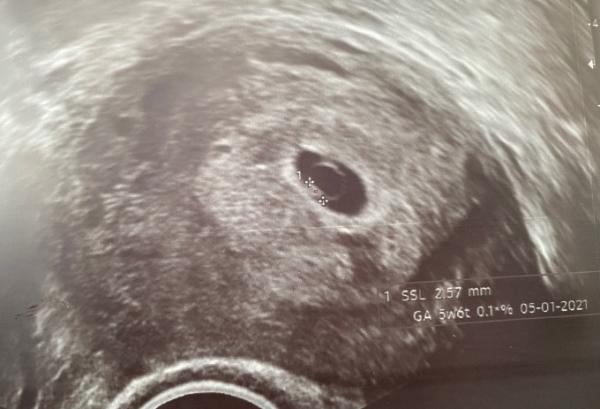

Im US hat man dann einen 2,5mm großen Embryo mit Herzschlag gesehen